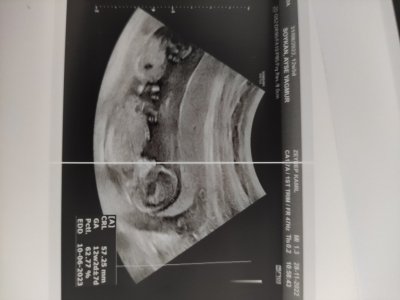

Hanımlar biliyorum çoğunuz beni dövecek  Fakat elimde değil meraktan catliyorum ramzi nub ne teori varsa bildiğiniz Allah rızası için tahmin yapar misiniz

Fakat elimde değil meraktan catliyorum ramzi nub ne teori varsa bildiğiniz Allah rızası için tahmin yapar misiniz  Bana kız da erkekte zerre farketmiyor fakat birinden biri olsun artık Çatlıcam su an 13 haftalık maalesef ultrason resmî vermediler cinsiyete de bakmadan zaten atıyorlar başlarından.Elimde sadece bu resim var.Yorum yapan herkes icin şimdiden çok çok teşekkür ederim

Bana kız da erkekte zerre farketmiyor fakat birinden biri olsun artık Çatlıcam su an 13 haftalık maalesef ultrason resmî vermediler cinsiyete de bakmadan zaten atıyorlar başlarından.Elimde sadece bu resim var.Yorum yapan herkes icin şimdiden çok çok teşekkür ederim